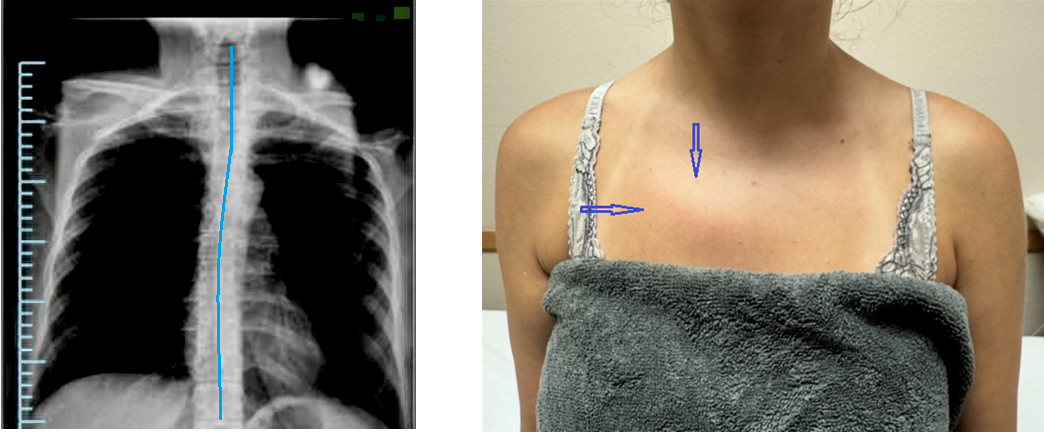

Please compare the right and left parasternal areas, paying particular attention to the right side of her upper chest. There is a visual bulge in her right parasternal region (indicated by blue arrows in the photo).

Thus, the patient’s anterior chest suggests the possible presence of an early stage of Scoliosis with thoracic curvature directed to the right.

The patient suggested visiting her family doctor, who referred her for an X-ray. Radiologist confirmed the 1st-stage of thoracic curvature (indicated by the blue line on the X-ray).

The presence of visual differences in the parasternal areas is due to the upper ribs’ anterior displacement caused by the rotation of the bodies of the upper thoracic vertebrae. In this scenario, it is useless to treat her middle back pain in the form of different syndromes of muscle dysfunctions since the upper thoracic curvature must be decompressed first.